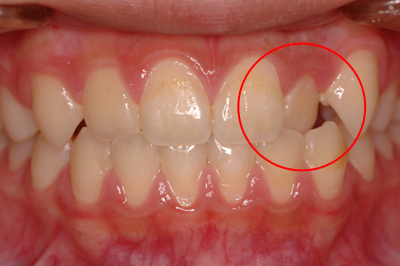

矯正治療例

施術前

施術中

施術後